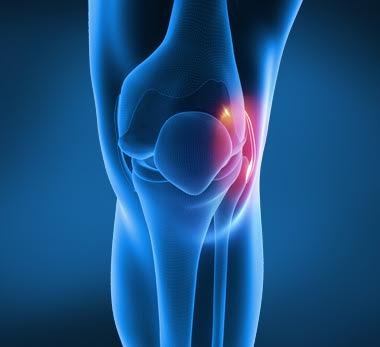

Κακώσεις γόνατος

Οι κακώσεις γόνατος είναι από τις πιο συνηθισμένες κακώσεις που ένας άνθρωπος θα αντιμετωπίσει. Όλοι μας κάποια στιγμή στη ζωή μας ακόμη και αν δεν αθλούμαστε, θα νιώσουμε κάποιο πόνο στην περιοχή του γόνατος που μπορεί να οφείλεται σε διάφορες αιτίες.

Οι κακώσεις γόνατος είναι από τις πιο συνηθισμένες κακώσεις που ένας άνθρωπος θα αντιμετωπίσει. Όλοι μας κάποια στιγμή στη ζωή μας ακόμη και αν δεν αθλούμαστε, θα νιώσουμε κάποιο πόνο στην περιοχή του γόνατος που μπορεί να οφείλεται σε διάφορες αιτίες.

Οι κακώσεις γόνατος μπορούν να διακριθούν με μια απλουστευμένη ταξινόμηση στις οξείες ή αιφνίδιες και στις χρόνιες κακώσεις.

Οξείες κακώσεις γόνατος

Συμβαίνουν αιφνιδίως μετά από τραυματισμό από άμεση πλήξη ή στροφική απότομη κίνηση του γόνατος. Πολύ συχνά προέρχονται μετά από αθλητικές δραστηριότητες. Τα κυριότερα συμπτώματα είναι ο πόνος, ο περιορισμός της κίνησης, το ύδραρθρο (υγρό στο γόνατο), και η εμφάνιση τους εξαρτάται από τον μηχανισμό κάκωσης και το βαθμό βίας που ασκήθηκε.